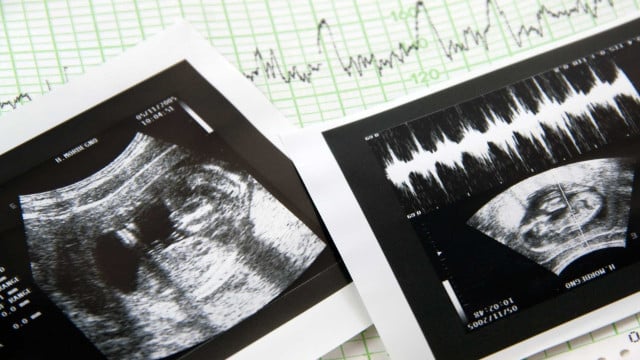

L’Inspection générale des activités de santé (IGAS) a ouvert une procédure d’inspection à la clinique Ceraque, à Pinhal Novo, qui n’aurait pas détecté une malformation grave chez un fœtus lors de l’échographie morphologique (qui permet de voir l’anatomie du bébé).

Tout au long de la grossesse, y compris lors de l’échographie morphologique réalisée dans cette clinique, il a été dit aux parents que leur enfant n’avait aucun problème. Ce n’est qu’à la naissance de l’enfant que les parents ont découvert que le bébé avait la jambe droite incomplète et seulement deux doigts au pied.